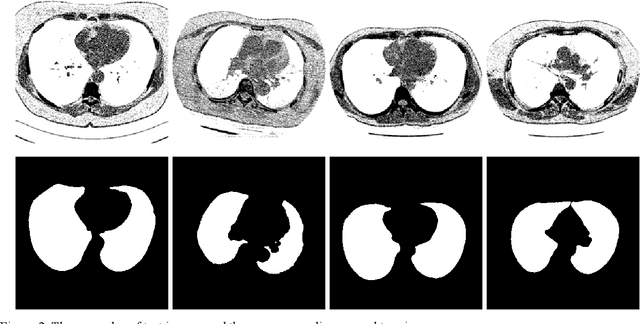

Abstract:Lung image segmentation plays an important role in computer-aid pulmonary diseases diagnosis and treatment. This paper proposed a lung image segmentation method by generative adversarial networks. We employed a variety of generative adversarial networks and use its capability of image translation to perform image segmentation. The generative adversarial networks was employed to translate the original lung image to the segmented image. The generative adversarial networks based segmentation method was test on real lung image data set. Experimental results shows that the proposed method is effective and outperform state-of-the art method.